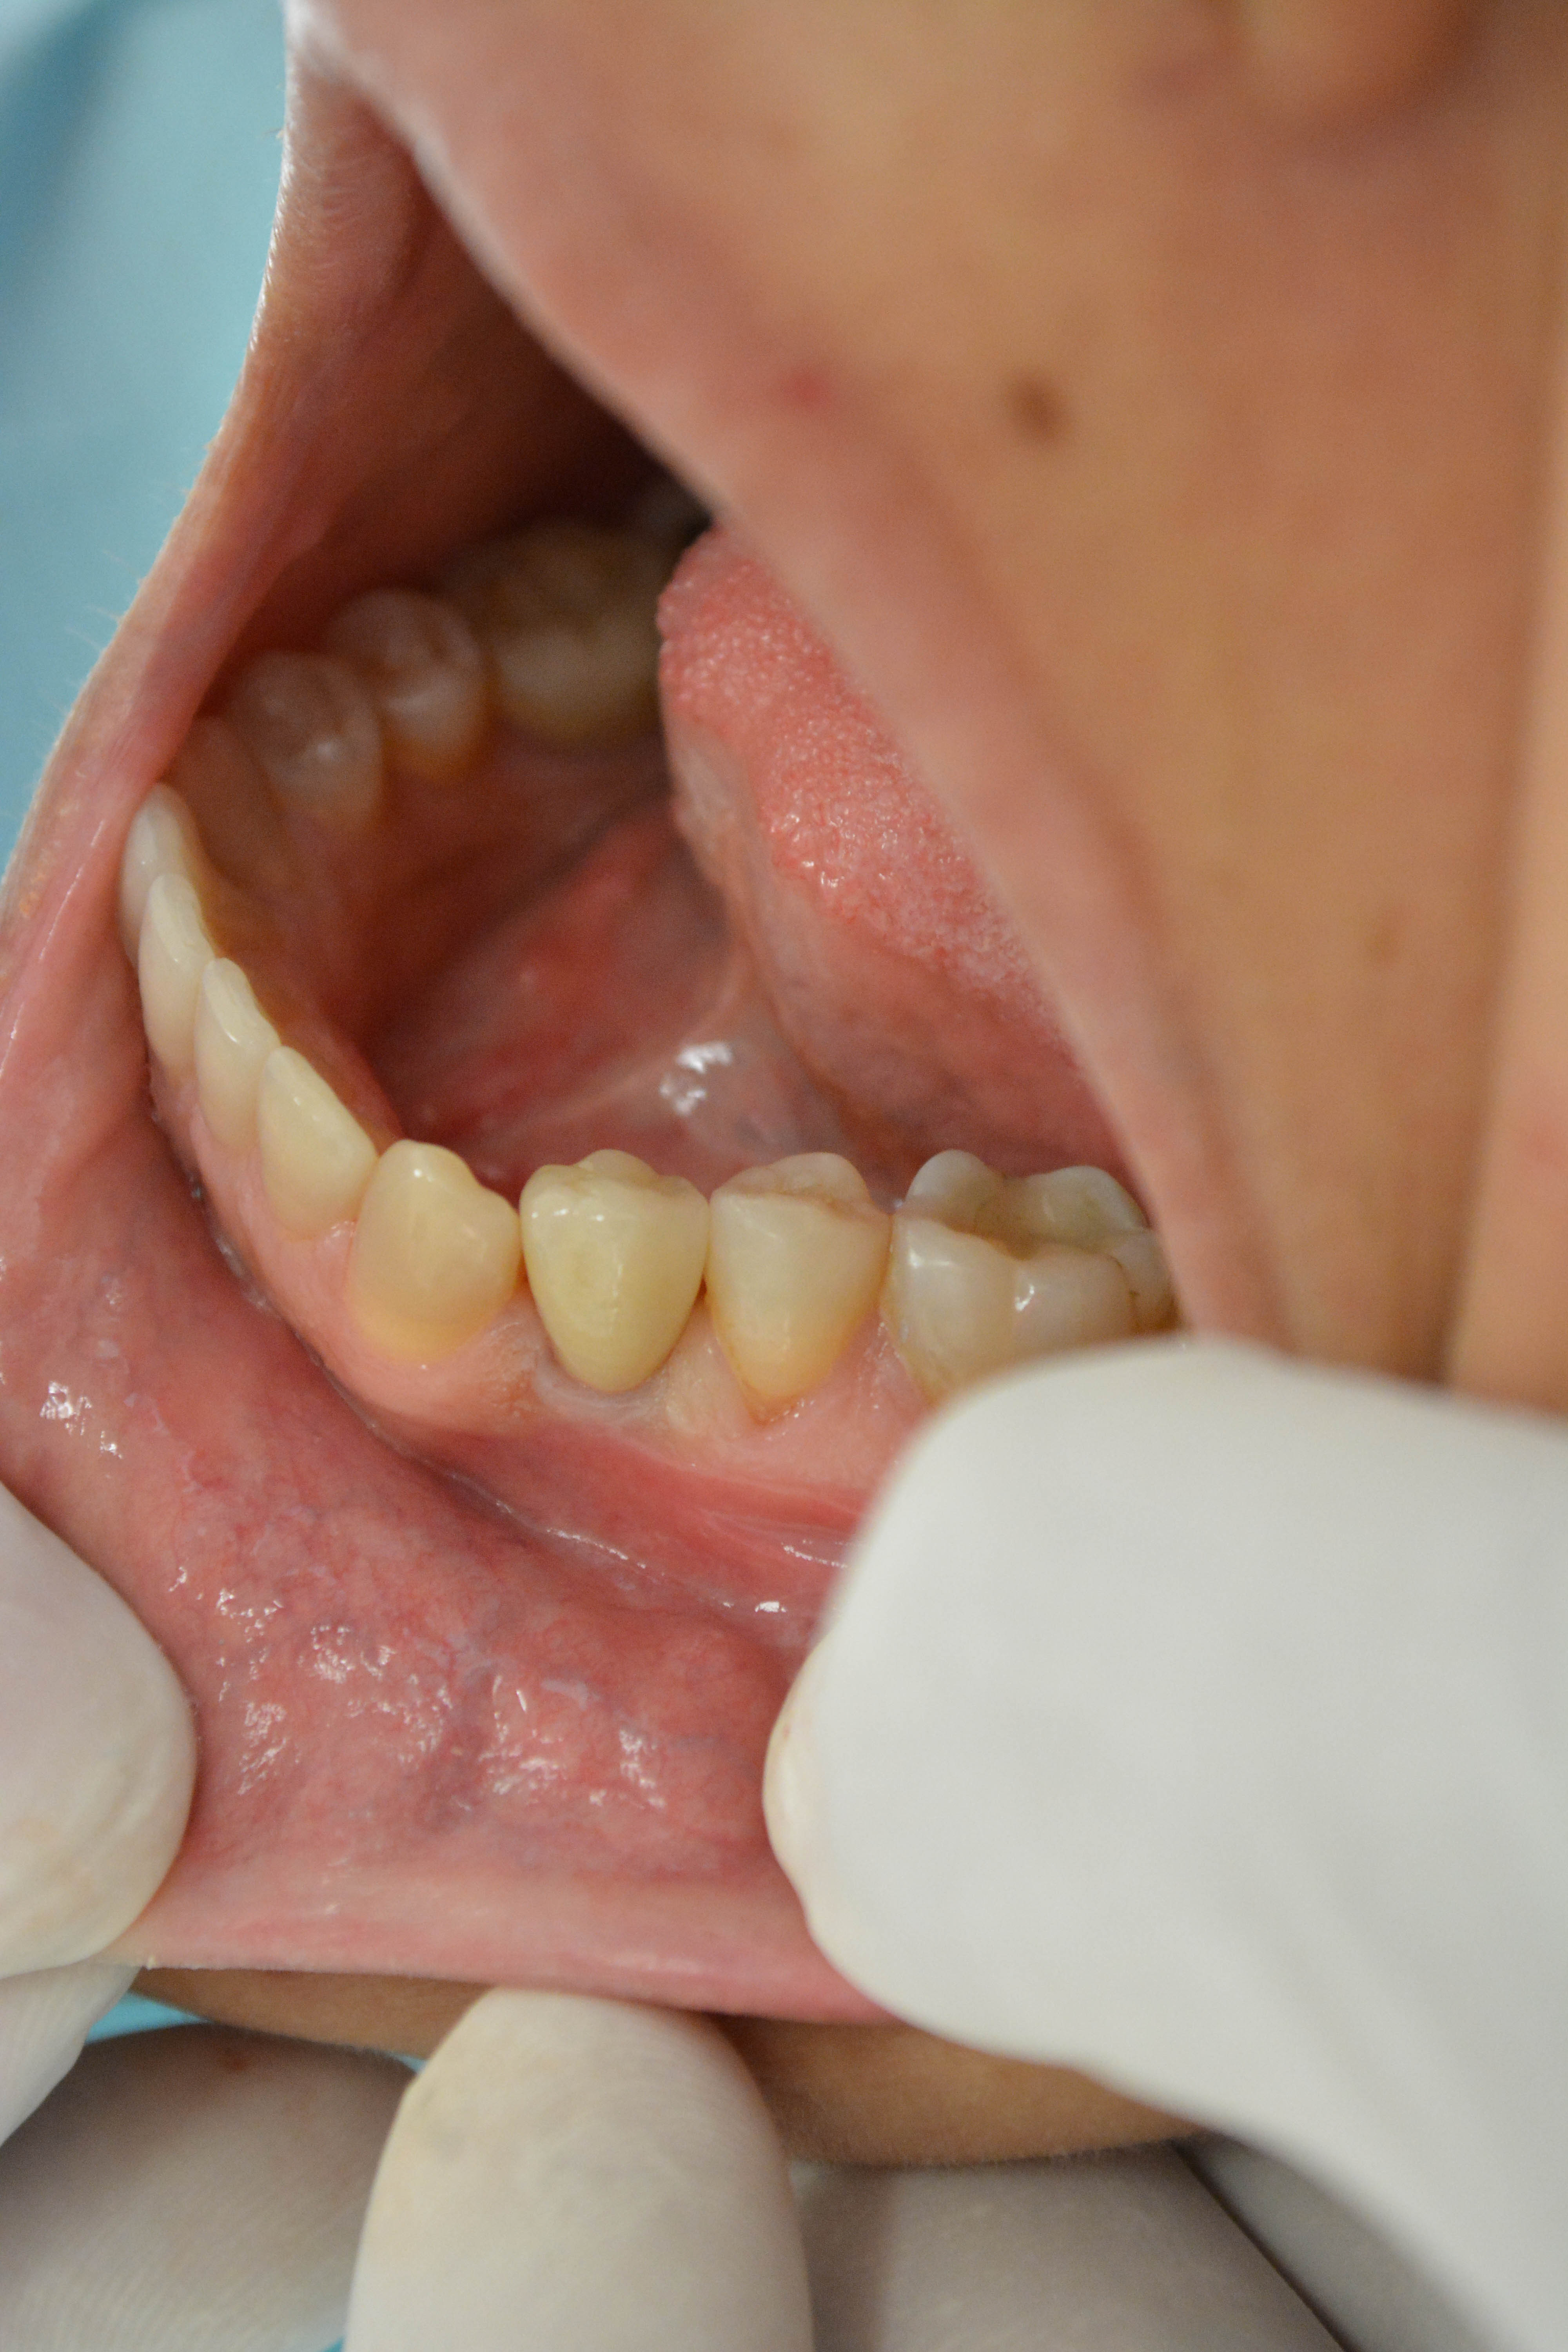

Methods: It was a case report of a 25 year old female patient who presented to dental clinic AKUH with the complaints of mobility in a tooth in lower left jaw. On clinical and radiographic examination her first premolar was periodontaly compromised and had a hopeless prognosis.An atraumatic tooth extraction was done under local anaesthesia and a Zimmer implant was immediately placed, primary stability achieved to 30Ncm. Temporary crown was placed on the implant on the same day using patient’s own pre extraction record. Her bite was adjusted to keep tooth slightly off occlusion.After a 2 weeks interval, excellent tissue healing was achieved and permanent crown was placed using cemented retention.

Results: The patient benefited with an esthetic smile as she never remained toothless during the entire treatment span. The final crown was fixed within two weeks of surgery rather than 4-6 months which is the conventional healing time. The pain experience was low too as all the treatment was completed in a single surgery with minimal tissue damage